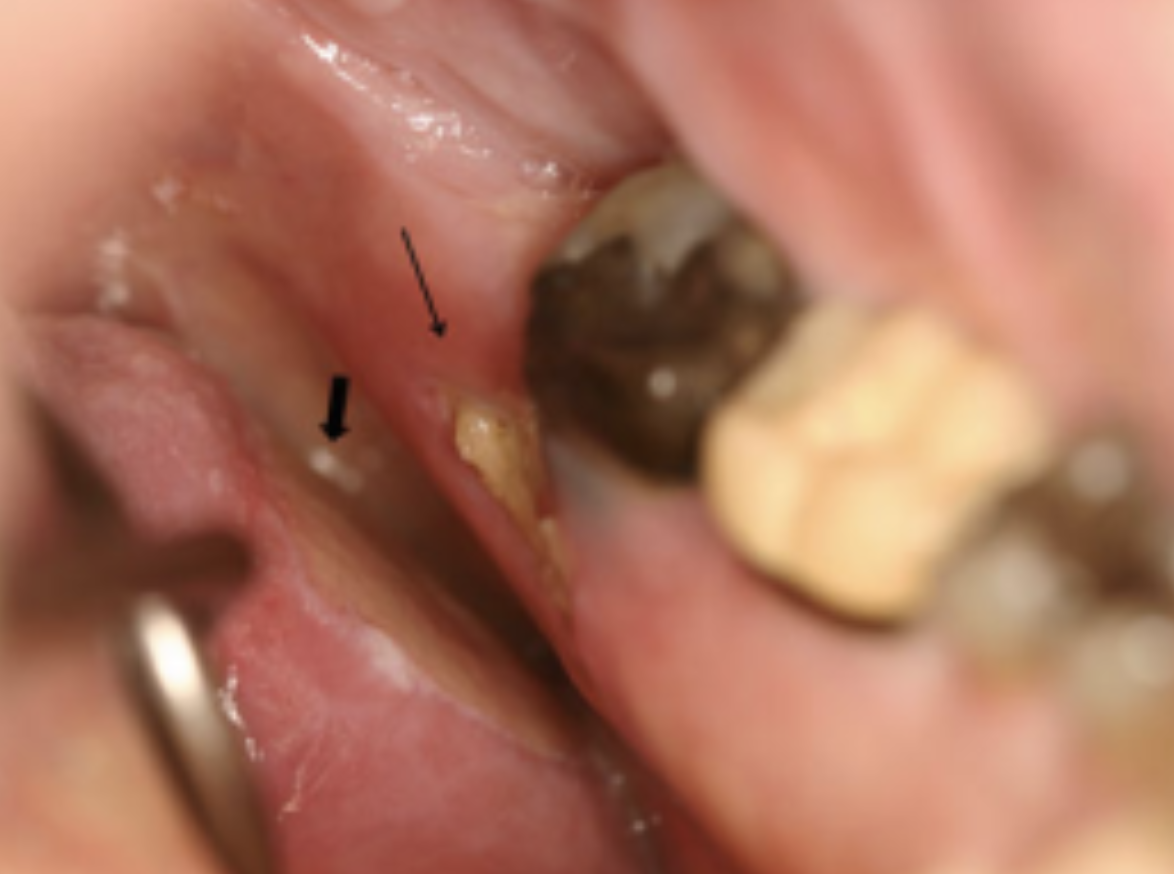

Các tổn thương xuất hiện dưới dạng các vùng xương hoại tử lộ ra màu vàng hoặc trắng có chiều dài từ vài milimet đến vài centimet (Hình 1). Bề mặt có thể gồ ghề, gây kích ứng lưỡi và đôi khi loét do chấn thương (Hình 2 ). Các mô mềm xung quanh thường đỏ và sưng lên để đáp ứng với sự nhiễm khuẩn nặng ở mô xương chết (Hình 3), hoặc hàm dưới có thể trở nên "giòn" hơn và có nguy cơ gãy xương. Dù các nghiên cứu cho thấy việc chụp X quang là không cần thiết cho chẩn đoán, nhưng nếu đáp ứng điều trị ban đầu chưa tốt hoặc nghi ngờ có biến chứng (Hình 4) thì nên chụp X quang toàn hàm hoặc CT Scan.